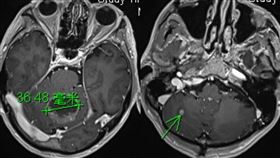

獨家/他的肺癌轉移到腦變「滿天星」

基隆長庚醫院傳出一名患有「刁鑽兇殘的癌中之王」小細胞...